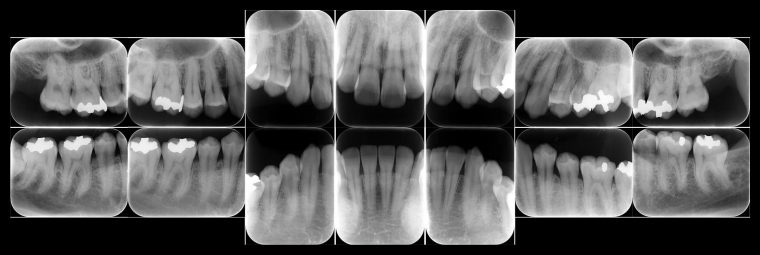

5.エックス線検査

レントゲン写真を撮って、骨の状態を調べます。前回、または次回と比較し、進行状態や進行速度を判断します。

歯ぐきの炎症を治すことは比較的簡単ですが、一度失った骨を元に戻すことは非常に困難です。悪化を防ぐためには、歯周病治療が欠かせません。

レントゲン画像を指さしている様子の写真